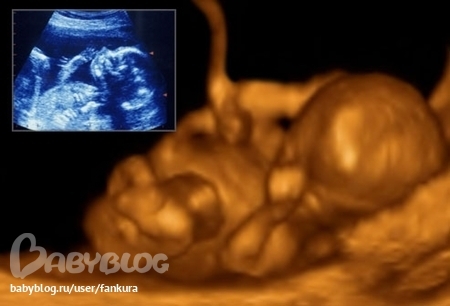

Анют а это вы в 3Д УЗИ? Мне интересно так все хорошо видно))) Мы на следующей недели пойдем))))

да сходите)все советуют)это же новое что то)))))классс